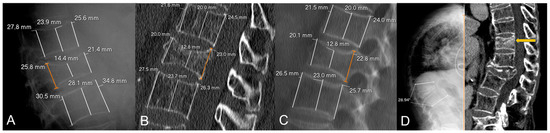

| Loss of anterior height (X-rays) | 26.1 ± 15.8 | 29.3 ± 17.8 | 22.9 ± 12.9 | 0.054 |

| Loss of middle height (X-rays) | 29.9 ± 12.3 | 32.4 ± 13.2 | 27.4 ± 11.0 | 0.052 |

| Loss of posterior height (X-rays) | 9.5 ± 10.3 | 12.3 ± 11.1 | 6.7 ± 8.7 | 0.009 * |

| Loss of anterior height (CT) | 19.5 ± 14.1 | 23.5 ± 14.9 | 15.6 ± 12.1 | 0.007 * |

| Loss of middle height (CT) | 25.5 ± 14.1 | 28.1 ± 15.5 | 22.8 ± 12.2 | 0.074 |

| Loss of posterior height (CT) | 7.8 ± 8.5 | 9.7 ± 10.0 | 5.9 ± 6.1 | 0.032 * |